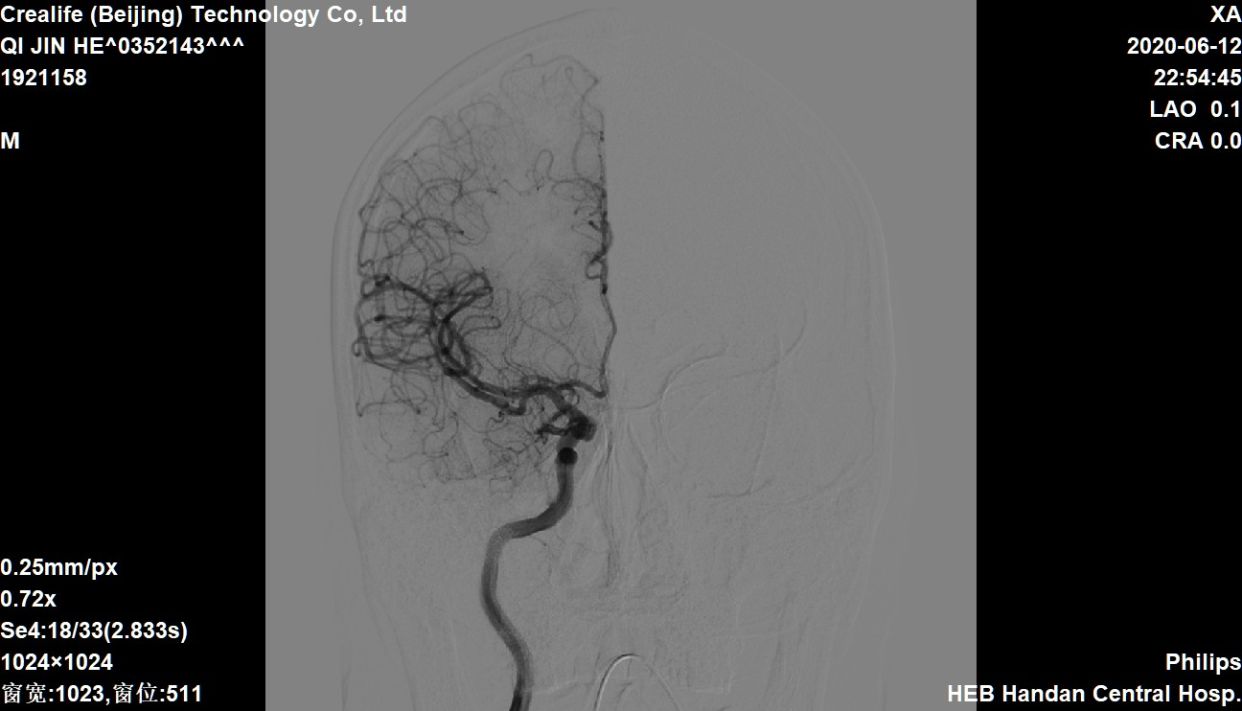

椎动脉造影,左侧软膜支有少量代偿

右侧大脑中动脉向左侧未见代偿

急性左侧大脑中动脉闭塞,考虑栓塞

侧位